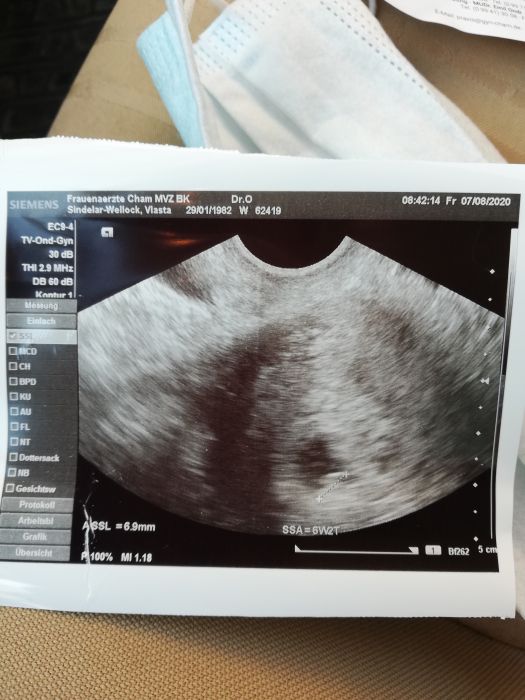

Ahoj maminy, tak je to tu. Dítko je na cestě

6+něco